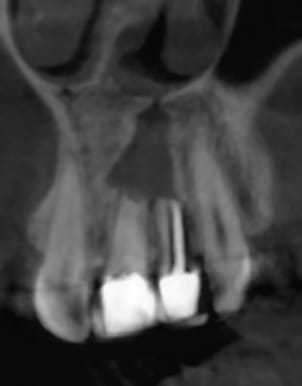

Je rajoutes quelques coupes et une rétro... C'est vraiment un massacre à la tronçonneuse!

24/04/2019 à 15h19

D'autres coupes et une rétro